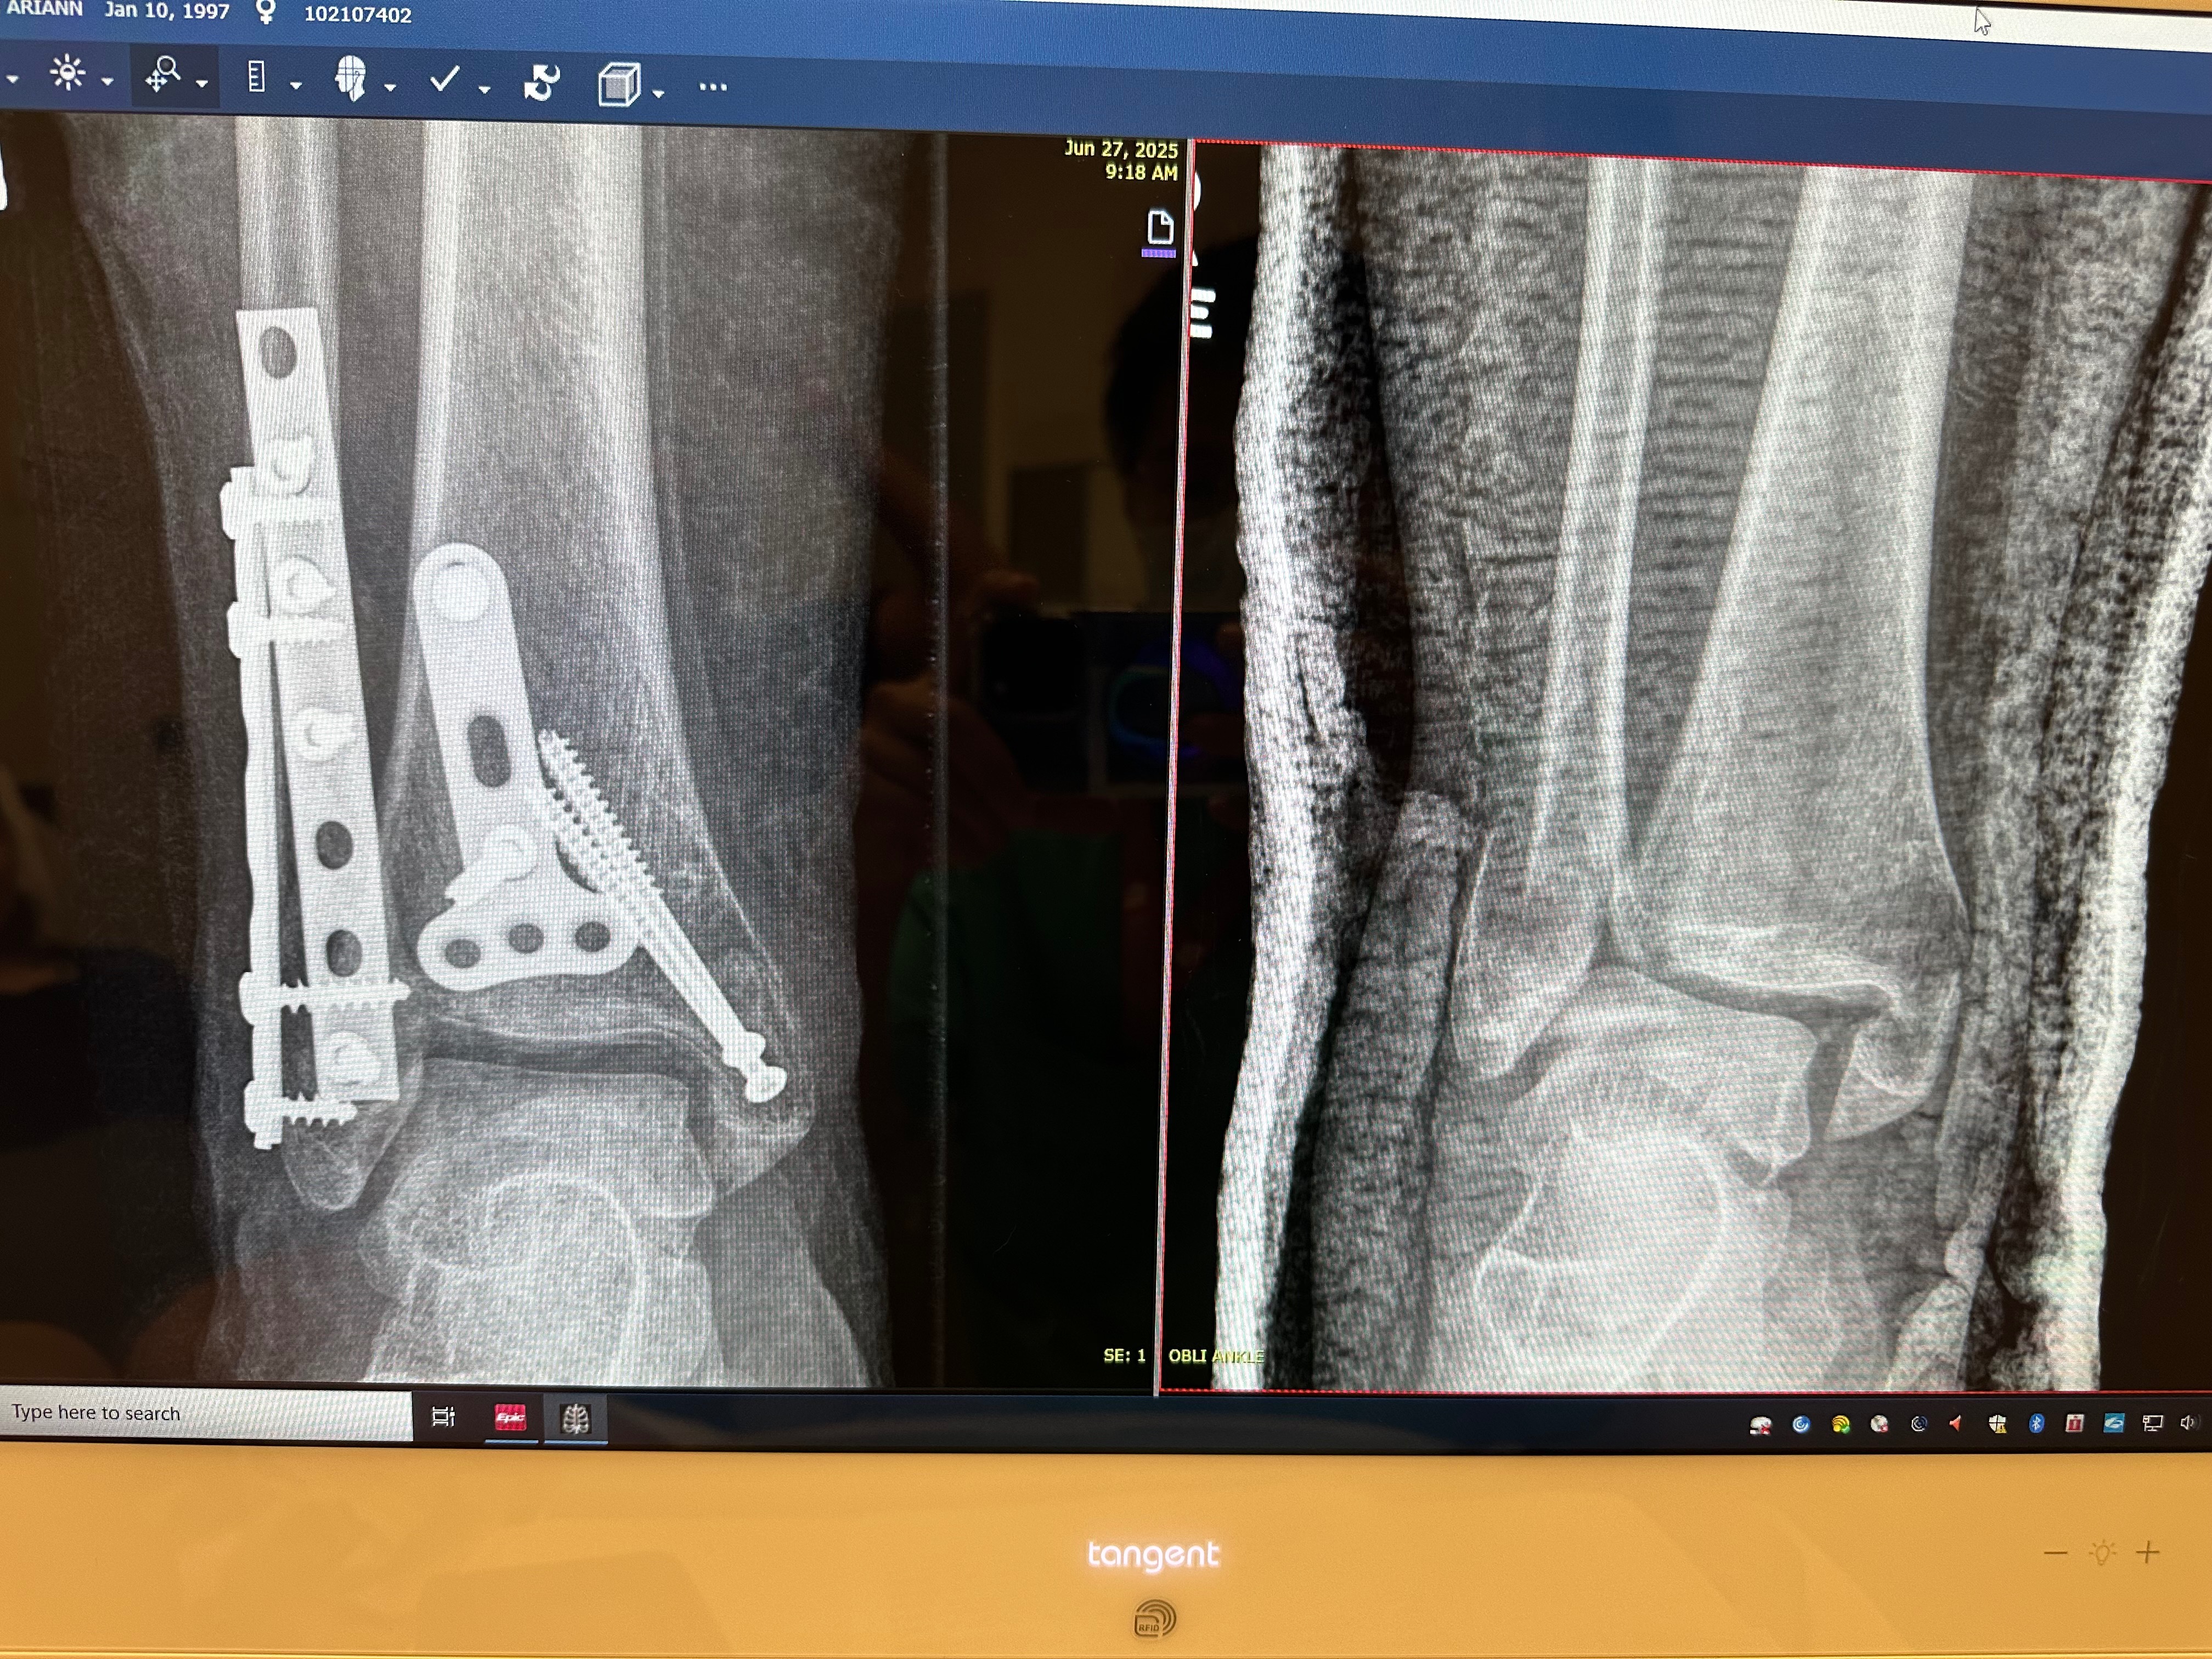

On April 25th, I had an accident stepping down stairs from a venue in San Francisco that resulted in a trimalleolar fracture on my right ankle. That means I broke my ankle in the critical three points that it connects to the foot and leg; basically, I broke it in the worst way possible.

Currently, I am being seen by SCVM without insurance and have been applying for financial assistance programs through the hospital as well as applying for disability (waiting on approval). The team at Valley Medical has been great to me but are limited in what to provide/expect for my needed future follow-up appointments as I have been unable to pay for most services provided so far. I am still going to require follow-up appointments with X-ray imaging, as well as physical therapy so that I can get back to walking and return to work and a somewhat normal life.